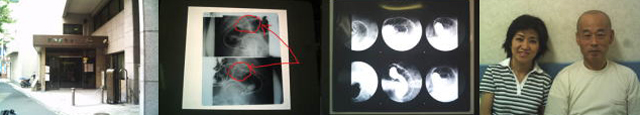

18枚のレントゲンを見る、内2枚に腫瘍らしき形状物有り。医師の説明が頭を

素通りし、顔がただただ赤らむのみ。

切除手術を即決し、手続きをおこない紹介状とレントゲンを借り受ける。

腸の各部分に突っ張り感を感じつつ順調に検査推移、モニターに写し出される

ピンク色の美しい腸内の映像を見、少し安堵する。

該当患部はやはり大きい、組織採集時の血の滲みを冷静に見つめている

自分と現実のギャツプに違和感を覚える。